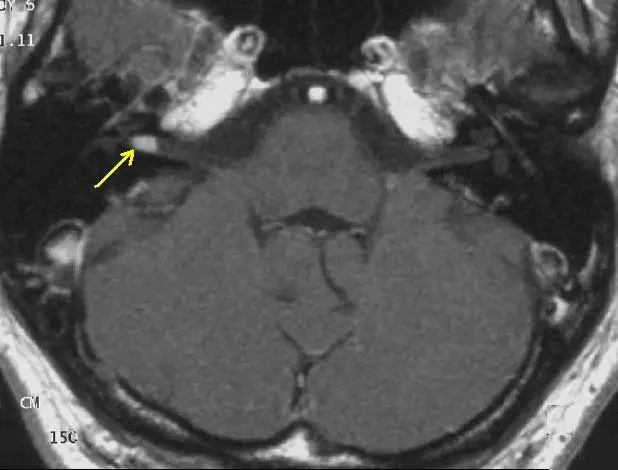

Secondo recenti statistiche vengono colpite circa 13 persone per milione di abitanti. Si tratta soprattutto di donne e di soggetti con un'età superiore ai 40 anni. 5 casi su 100 sono legati alla neurofibromatosi di tipo 2, una condizione congenita particolare. Il neurinoma acustico, noto anche come Schwannoma vestibolare, è un tumore benigno del cervello che interessa le cellule di Schwann dell'VIII nervo cranico. Queste cellule della glia, che avvolgono gli assoni, fanno parte del sistema nervoso periferico. Esse producono la mielina, ovvero una sostanza isolante che aumenta la velocità di conduzione del segnale nervoso e hanno il compito di fornire supporto e stabilità ai neuroni.

I sintomi del neurinoma acustico compaiono gradualmente, poiché la massa cancerosa si accresce in maniera lenta e discontinua. Il ritmo di crescita della neoplasia, infatti, è di circa 1-2 millimetri all'anno, tuttavia possono verificarsi casi in cui il tumore si espande più velocemente. Tale condizione, ovviamente, rende la diagnosi alquanto difficile. La prima conseguenza del neurinoma acustico è la compromissione delle funzioni uditive e di equilibrio. Ciò spiega perché i pazienti lamentano perdita di udito, acufeni e vertigini. I disturbi acustici vengono avvertiti, quasi sempre, su un lato soltanto, ma possono presentarsi su entrambi i lati se all'origine del tumore vi è la neurofibromatosi di tipo 2. Altri segni clinici comprendono: mal di testa, visione offuscata, intorpidimento, formicolio e/o dolore a un lato della faccia, atassia, difficoltà di deglutizione, cambiamenti del tono di voce.